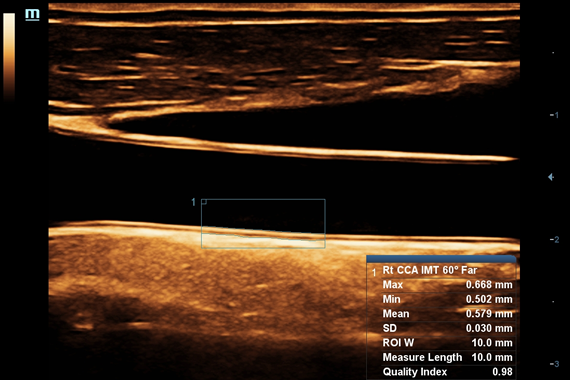

–ú–Ω–æ–≥–æ—Ñ—É–Ω–∫—Ü–∏–æ–Ω–∞–ª—å–Ω–∞—è —Å–∏—Å—Ç–µ–º–∞ DC-60 Exp —Å X-Insight –ø—Ä–µ–¥—Å—Ç–∞–≤–ª—è–µ—Ç —Å–æ–±–æ–π –∫–æ–º–ø–ª–µ–∫—Å–Ω–æ–µ —Ä–µ—à–µ–Ω–∏–µ, –∫–æ—Ç–æ—Ä–æ–µ –ø–æ–º–æ–≥–∞–µ—Ç —É–ø—Ä–∞–≤–ª—è—Ç—å –ø–æ–≤—Å–µ–¥–Ω–µ–≤–Ω–æ–π –∫–ª–∏–Ω–∏—á–µ—Å–∫–æ–π –ø—Ä–∞–∫—Ç–∏–∫–æ–π —Å –ª–µ–≥–∫–æ—Å—Ç—å—é –∏ —É–≤–µ—Ä–µ–Ω–Ω–æ—Å—Ç—å—é.

–û—Å–Ω–æ–≤—ã–≤–∞—è—Å—å –Ω–∞ –≥–ª—É–±–æ–∫–æ–º –ø–æ–Ω–∏–º–∞–Ω–∏–∏ –ø–æ—Ç—Ä–µ–±–Ω–æ—Å—Ç–µ–π –∫–ª–∏–µ–Ω—Ç–æ–≤, –∫–æ–º–ø–∞–Ω–∏—è Mindray —Ä–∞–∑—Ä–∞–±–æ—Ç–∞–ª–∞ —Å–∏—Å—Ç–µ–º—É DC-60 Exp —Å X-Insight, —á—Ç–æ–±—ã –æ–±–µ—Å–ø–µ—á–∏—Ç—å –≤—ã—Å–æ–∫—É—é –ø—Ä–æ–∏–∑–≤–æ–¥–∏—Ç–µ–ª—å–Ω–æ—Å—Ç—å –∏ —Ç–æ—á–Ω–æ—Å—Ç—å –≤–∏–∑—É–∞–ª–∏–∑–∞—Ü–∏–∏ –≤–∫—É–ø–µ —Å –Ω–∞–≥–ª—è–¥–Ω–æ—Å—Ç—å—é, –∏—Å–∫–ª—é—á–∏—Ç–µ–ª—å–Ω–æ–π –∏–Ω—Ç–µ–ª–ª–µ–∫—Ç—É–∞–ª—å–Ω–æ—Å—Ç—å—é –∏ –æ–≥—Ä–æ–º–Ω—ã–º –æ–ø—ã—Ç–æ–º.